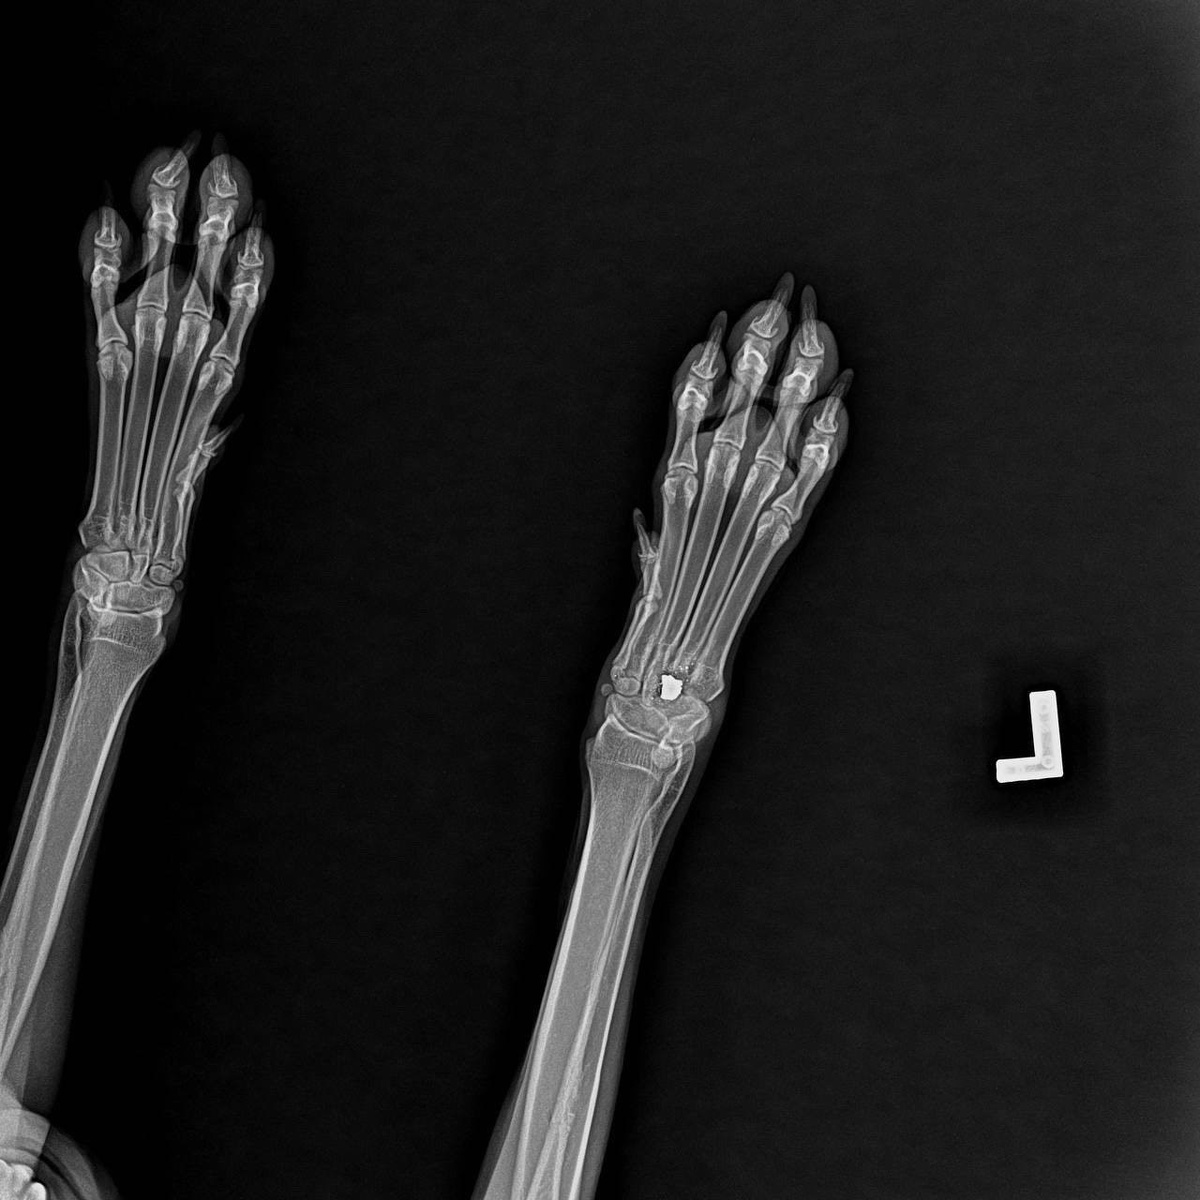

📌 На обследовании выяснилось:

🔹 в холке – пневматическая пулька

🔹 в лапе – ещё одна

🔹 в области брюшины – третья

Каждая – как напоминание о пережитом, известном только Айве.

Операция прошла успешно, и собака начала восстанавливаться.